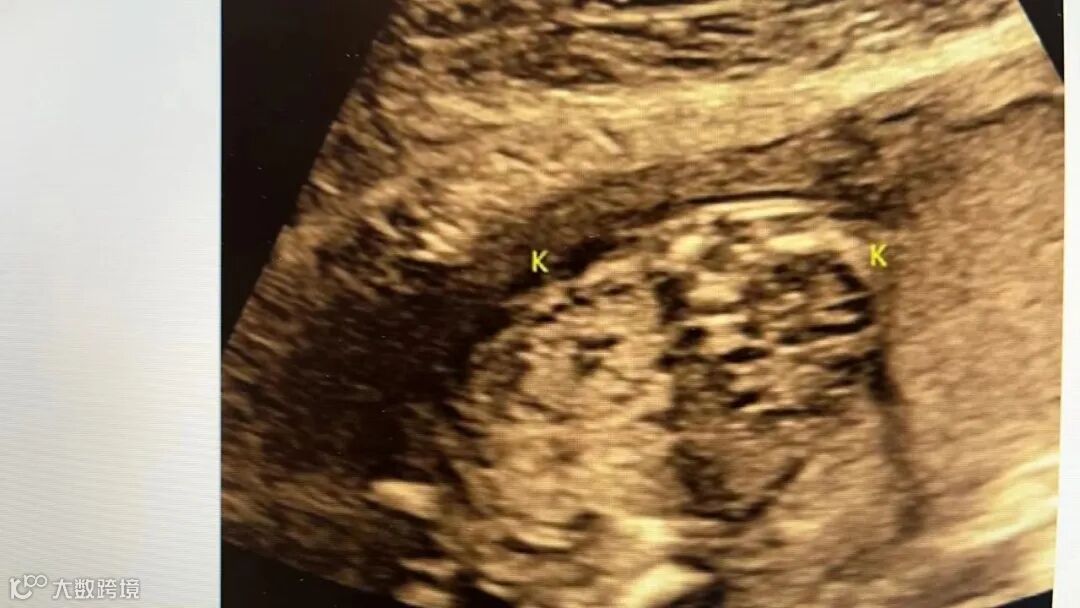

MCDK 双侧